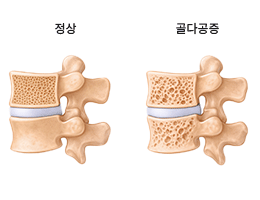

골다공증 (Osteoporosis)